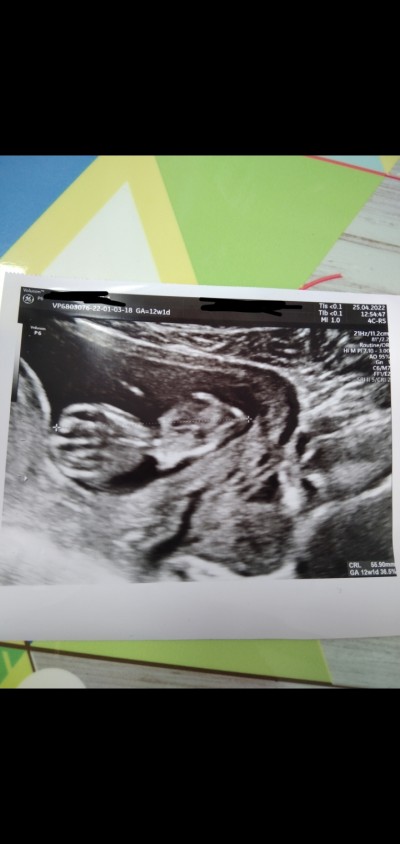

12+1 haftalık hamileyim bugün doktora gittik göstermedi sırtını dönmüş

Sizce cinsiyeti nedir?

Sırtı dönük o yüzden bacak arası görünmüyor, crl sini söylersen cinsiyeti söyleyebilirim sana :)

Bizimde 13 haftalık crl 70.1 mm

Yuzde 90 kiz